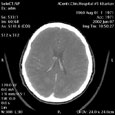

Нормальное состояние сосудов виллизиевого круга.

Пациент P., 30 лет

ЦКБ5 Южной железной дороги, отделение лучевой диагностики.

Протокол.

На КТ-сканах вещество головного мозга без очаговых изменений, плотностью 24-37 HU. Срединные структуры головного мозга не смещены. Желудочки мозга обычной формы, не расширены (ширина III желудочка - 2 мм, передних рогов боковых: правого 3 мм, левого 6 мм). Конвекситальные подпаутинные пространства не расширены. Цистерны мозга асимметричны с расширением сильвиевой щели в передних отделах слева. Субтенториальные структуры без особенностей. Селлярная область не изменена. Пневматизация основной, фронтальной пазух и клеток решетчатого лабиринта не нарушена. Костно - деструктивные изменения не определяются. В условиях ангиографии (Омнипак 300 - 100,0) контрастированы сосуды виллизиева круга и их интракраниальные ветви. Патологические изменения положения, калибра, наполнения не выявлены.